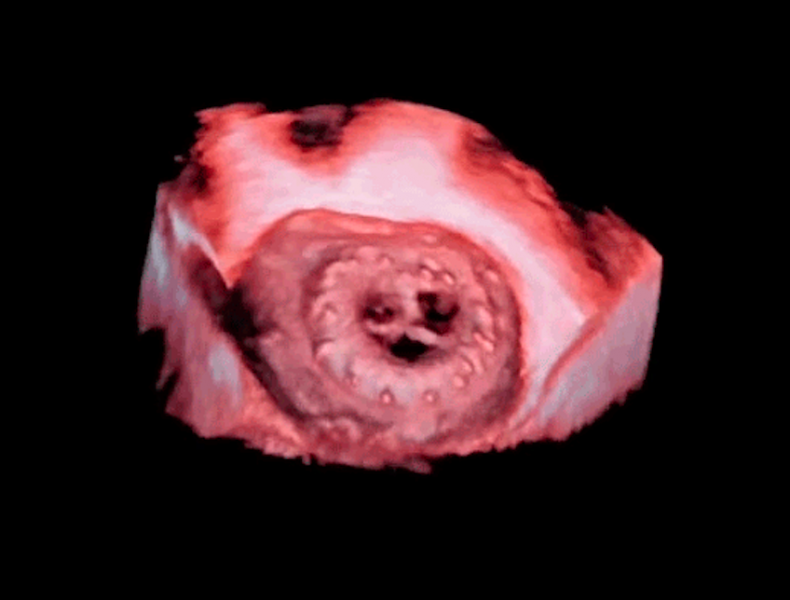

There were several overall key trends evident at the 2016 meeting of the American Society of Echocardiography in June ...

Interview with Claudio Smuclovisky, M.D., FACC, FSCCT, director of South Florida Imaging Cardiovascular Institute, Holy ...

An interview with Jonathan Leipsic, M.D., FSCCT, chairman of the department of radiology, St. Paul’s Hospital, Vancouver ...